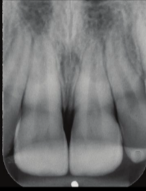

concussion

tooth receives damage to periodontal ligament

tooth remains stable

imaging likely normal